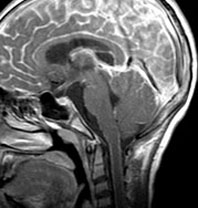

生下時に皮膚の大きな先天性色素細胞母斑があり脳MRIでみられたもの

有毛性母斑があるためにMRIが撮影されました。生後2ヶ月のものです。脳溝に沿うように,灰白質に浸潤するように,散在性の病変がみられます。脳幹部の前面から脳幹内部に浸潤するメラノーシスも特徴的です。